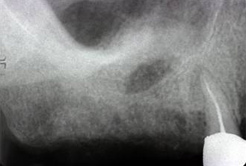

上顎には上顎洞という空洞があります。 人によっては上顎洞が大きくてインプラントに必要な骨の高さが足りないこともあります。 その場合、上顎洞内に骨補填材を用いて骨造成(サイナスリフト)を行います。

インプラント治療するには 上顎洞の間に骨幅がありません。

CT等の検査後にサイナスリフトを 行いました。